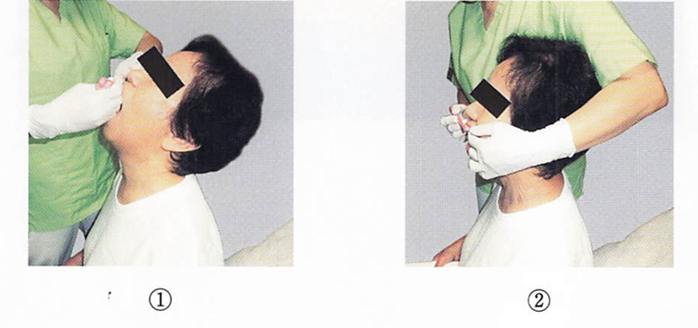

摂食嚥下障害を有する患者の口腔衛生管理時の写真を別に示す。 患者の姿勢で正しいのはどれか。2つ選べ。

a. ①

b. ②

c. ③

d. ④

解答を見る

b.d